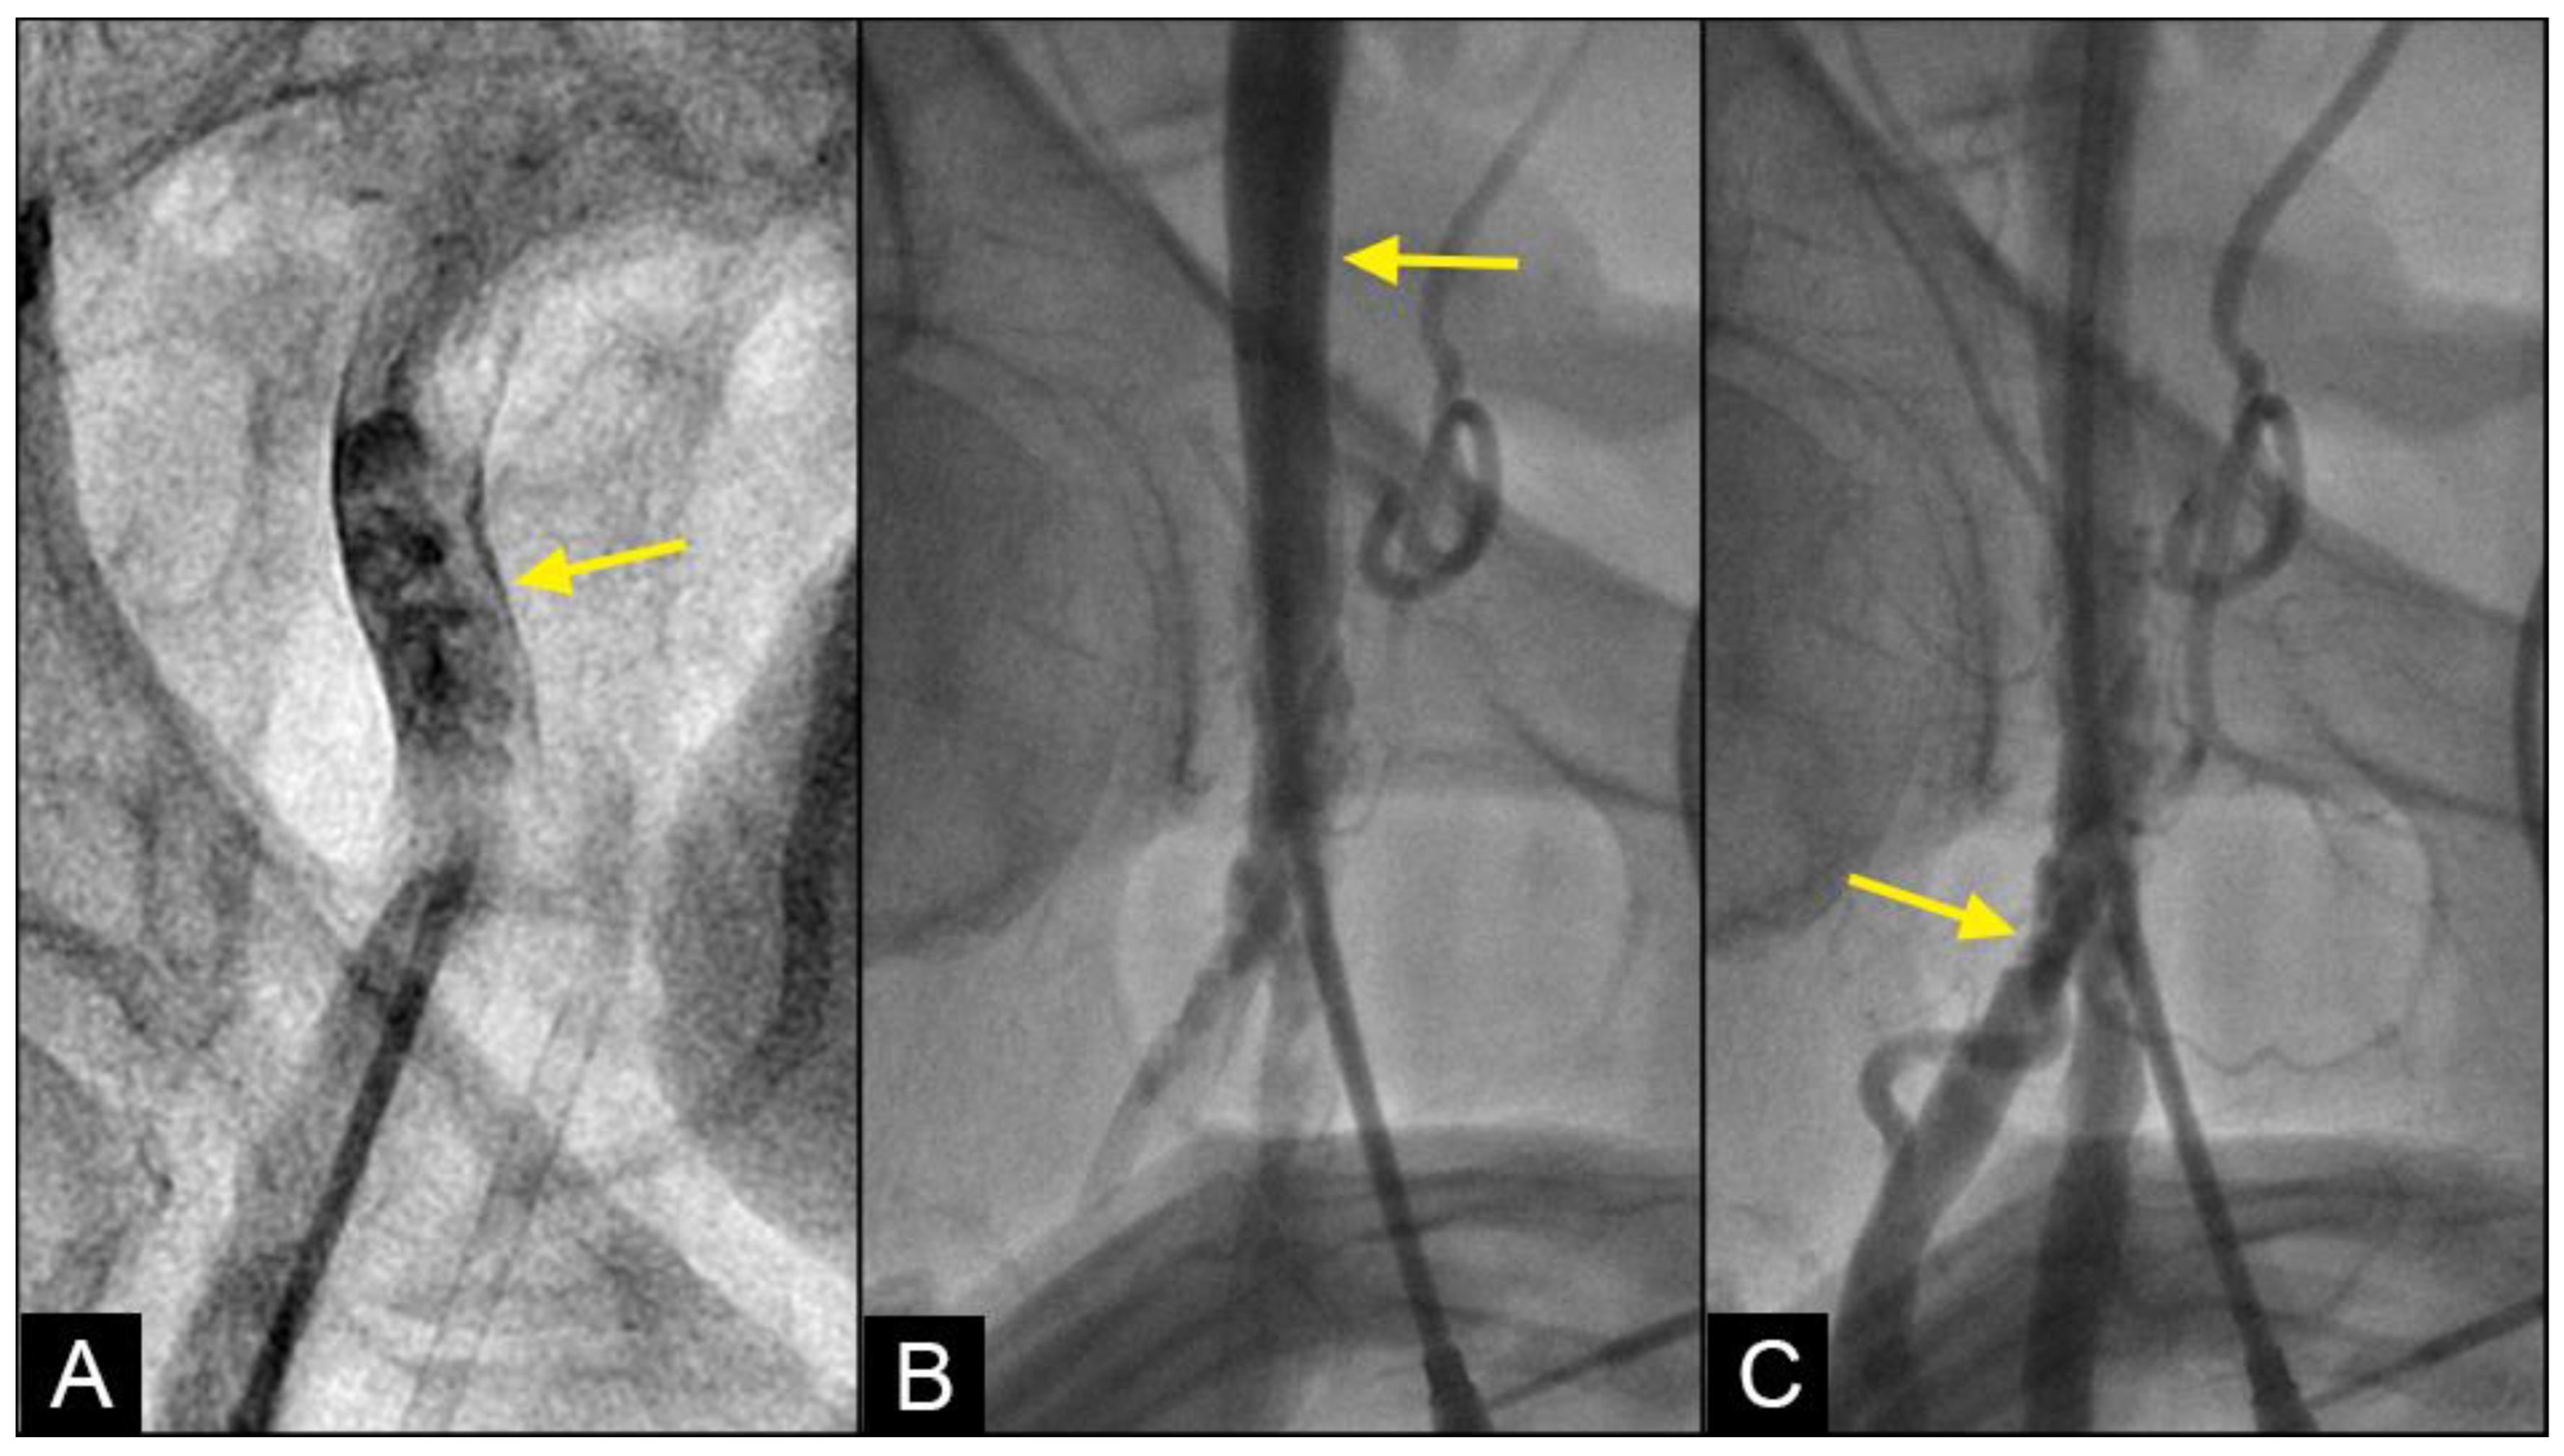

RETROGRADE contrast flow: In this iliac angiogram recorded by the novel dynamic angiographic technique, near the end of systole and in the first half of diastole, the retrograde flow is observed as a black contrast moving upwards from the iliac arteries towards the aortic bifurcation (Figure 6A–D). In contrast, for the right coronary artery (RCA), the retrograde flow happened mainly in the first half of systole. The retrograde flow in the coronary artery will be discussed in more detail in the next section.

Figure 6.

(A–D) Retrograde flow in the iliac artery. These are consecutive images separated from each other by 0.067 s. (A) Near the end of systole, the contrast (in black) could be seen moving upwards with a blunted, curved head (arrow). (B–D) In each image, separated by 0.67 s, the column of contrast was seen mixed with white-colored blood moving further up with a blunted, curved head (arrow).

COLLISION: In the iliac artery, near the end of systole and during the first half of diastole, the retrograde flow was observed moving upwards with a well-defined round head, despite the distinct separation between the two flows (Figure 8A,B). This retrograde flow was not laminar due to the heterogeneous composition of the fluid. There was a slight mixing of white blood and black contrast, with most of the fluid at the proximal head of the retrograde flow appearing predominantly black. The retrograde flow continued upwards (arrow) until it was overridden by the antegrade flow of the subsequent systole (Figure 8C,D). Overall, the interface between the antegrade and retrograde flows exhibited a subtle demarcation line, indicating a gentle interaction between the two opposing forces.

Figure 8.

(A–D) Interface of the collision between the antegrade blood flow and the retrograde contrast flow. These figures are in consecutive sequence. The antegrade flow represents the systolic contraction, while the diastolic contrast flow represents the exaggerated peripheral vascular resistance. (A) The blood advances with a soft, vague tip (yellow arrow). (B) Then, 0.067 s later, the retrograde flow begins to form, slowly pushing upwards (red arrow). (C–E) At the same time, the antegrade flow moves forward slowly (yellow arrow). At the interface, the proximal end of the retrograde flow has a round curve shape suggestive of a soft interaction with the antegrade flow (red arrow). The blood in white still flows forward at a slower pace (yellow arrow), while the retrograde flow moves upwards (red arrow).